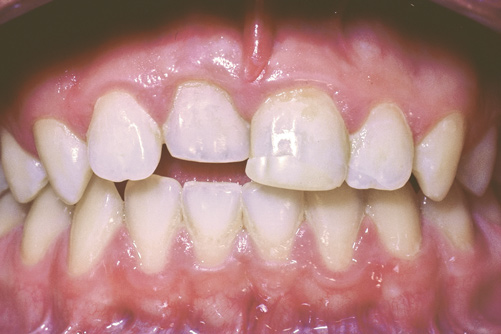

Fig 21. Age 21. Presurgical labial view prior to implant placement.

Figure 21

At age 21, it was determined that growth was substantially com--pleted (Figure 21). At the implant surgery, a mid-crestal incision was made with adjacent sulcular incisions. The labial flap was reflected revealing a very wide ridge at the coronal aspect. The mid-labial fenestration was evident along with exposed gutta-percha. A test drill was made and a radiograph was taken, which showed that the gutta-percha was removed during the site preparation. The fixture was placed and a 2 mm healing abutment secured (Figure 22). The bone was quite dense. The labial fenestration was grafted with particulate bone and primary closure was accomplished with 6-0 nylon sutures.

The patient healed well, and in 4 months the implant was uncovered with a simple punch uncovering technique. One month later, the restorative dentist placed a custom provisional restoration to begin molding the soft tissue. There was a small black space between the central incisors, partly due to the triangular shape of tooth No. 9 and slight papilla shrinkage on the mesial of No. 9. A small gingival composite was placed on the mesial of No. 9 to mimic the contour of the provisional crown. The tissue was molded for 4 months, and the final restoration was placed (Figure 23).